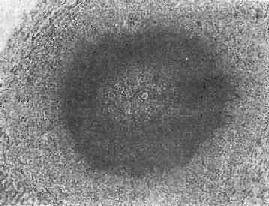

(1)急性虫卵结节:肉眼观为灰黄色、粟粒至绿豆大(0.5~4mm)的小结节。镜下见结节中央常有1~2个成熟虫卵,也偶可多达20个以上。这些成熟虫卵的卵壳上附有放射状嗜酸性的棒状体,也称为Hoeppli现象,用免疫荧光法已证实为抗原抗体复合物。虫卵周围是一片无结构的颗粒状坏死物质及大量嗜酸性粒细胞浸润。因其病变类似脓肿,故也称为嗜酸性脓肿(图19-5)。在坏死组织中可混杂多数菱形或多面形屈光性蛋白质晶体,即Charcot-Leyden结晶,系嗜酸性粒细胞的嗜酸性颗粒互相融合而成。随后虫卵周围产生肉芽组织层,其中有以嗜酸性粒细胞为主的炎症细胞浸润,还有单核巨噬细胞、淋巴细胞、浆细胞及少量中性粒细胞。随着病程的发展,肉芽组织层逐渐向虫卵结节中央生长,并出现围绕结节呈放射状排列的类上皮细胞层。类上皮细胞层逐渐加宽,嗜酸性粒细胞显著减少,构成晚期急性虫卵结节(图19-6),这是向慢性虫卵结节发展的过渡阶段。

肝血吸虫病之急性虫卵结节

图19-5 肝血吸虫病之急性虫卵结节

结节中心有一成熟虫卵,卵壳表面可见放射状物质,周围广泛坏死伴大量嗜酸性粒细胞浸润